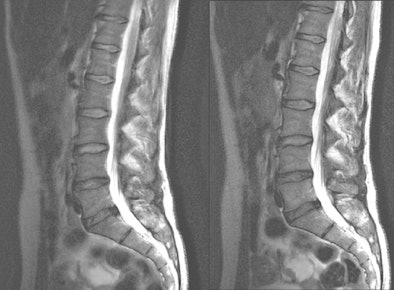

| The lumbar spine of a 68-year-old woman with sequestered disk herniation is shown in parallel transmission mode (right) and single-source transmission mode (left). Independent readers rated the parallel image as superior. Images courtesy of Radiology (December 2010, Vol. 257:3, pp. 743-753). |

Spinal 3-tesla MRI with parallel transmission also yielded a median assessment of at least adequate image quality in all of the compared sequences. There were no cases in which an image was determined to be of nondiagnostic quality.

With the "significant acceleration" of scan time and parallel transmission with 3-tesla MRI of the spine, Nelles said, there is "really a strong advantage for patients with back pain and in cases of claustrophobia. The diagnostic image quality of these fast sequences stays comparable to that of the single standard transmission sequences."